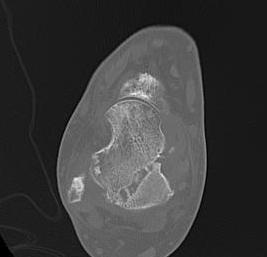

CT

Malunion / AVN